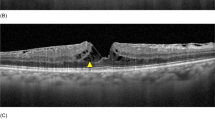

Type 4 pathway of FTMH formation in the left eye of a 41-year-old man with PDR. (a) TRD was noted on OCT. (b) 1 month later, TRD with mild foveal thinning (arrow) was detected on OCT. (c,d) 1 month later, fundus photography showed severe PDR with grade 4 FVP and MHRD (MH minimal diameter 239 μm) developed. Foveal thinning (arrow) was noted on OCT. (e,f) 1 year after surgery, fundus photography showed attached retina under silicone oil tamponade, and OCT revealed U-shaped MH closure.